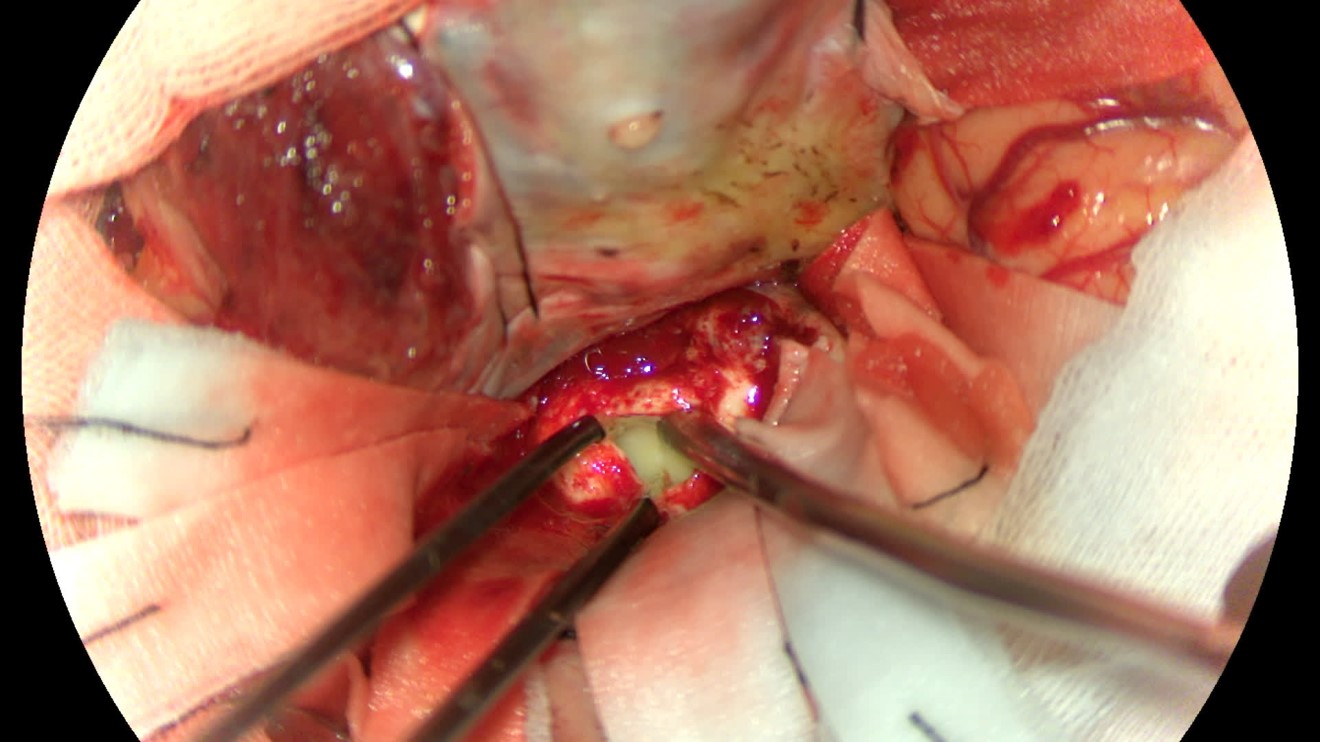

该患者入院后完善常规颅脑影像学检查,左侧颞叶病变,疾病性质不详,转移瘤、胶质瘤、炎症类疾病均不能排除,遂行PET-CT检查,提示左侧颞叶高代谢,淋巴瘤不能排除。组织MDT会诊建议可先行腰椎穿刺查脑脊液脱落细胞学、感染指标,若仍不能确诊,可进一步行开颅病灶切除,术中快速冰冻,根据冰冻结果决定手术手术策略。患者脑脊液脱落细胞学结果:较多淋巴细胞,少许单核细胞及个别中性粒细胞,未见异形细胞,脑脊液常规、生化、脑脊液培养未见细菌生长,诊断仍不能明确,且患者病情进展迅速,患者神志呈昏睡状态,颅脑MRI提示病变较前明显增大(影像学检查间隔两周),且水肿明显加重,遂行开颅病变切除术。术中见部分病变累及蝶骨嵴硬膜,病变质地硬韧,内有多个囊腔,囊内容物为黄色粘稠样脓性物质,留取囊液及实性部分送快速冰冻,在等待冰冻过程中,进一步探查见肿瘤侵犯左侧颞叶,该部位肿瘤质地相对软,无包膜,与周围脑组织无边界,血运不丰富,内有多个囊腔,且肿瘤侵犯侧裂池、颈动脉池,左侧视神经、颈内动脉、大脑中动脉均被病变包绕,且该处肿瘤质地偏硬韧。术中快速冰冻提示组织大片变性坏死,伴胶质增生及淋巴增生。结合病变质地及冰冻结果,考虑为非肿瘤性疾病,可能为炎性病变伴肉芽肿形成可能性大,且肿瘤质地硬韧,累及范围广泛,难以全切,遂行肿瘤大部分切除后结束手术。术后病理结果明确后予以伏立康唑、醋酸卡泊芬净抗真菌治疗。在治疗过程中患者先后出现脑出血、脑梗塞,最终因治疗周期长,花费高、效果不确定等因素,家属放弃治疗,于术后1月去世。